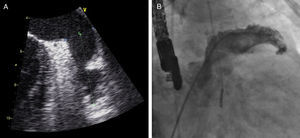

Sob sedação profunda/anestesia, efetuou-se o ecocardiograma transesofágico, realizado aos 0°, 45°, 90° e 135°, para excluir novamente a presença de trombos no AAE, medir a profundidade e o maior diâmetro do ostium (Figura 3).

Foi efetuada punção transeptal, sob controlo fluoroscópico e ecocardiografia transesofágica, e colocado guia superstiff, através do qual foi avançado um cateter multipurpose até ao AAE. De seguida, foram efetuadas 2 injeções de contraste (RAO 20° caudal 20°, RAO 20° cranial 20°) com preenchimento do AAE (Figura 3) para sua medição.